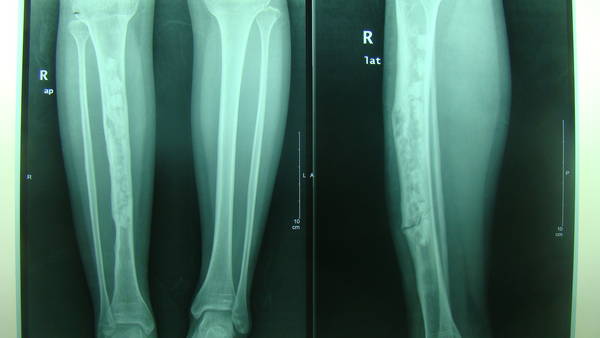

[修复重建] 游离腓骨移植术

补发术前术后照片